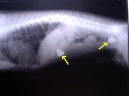

Kostní trus v sestupné části tlustého střeva.